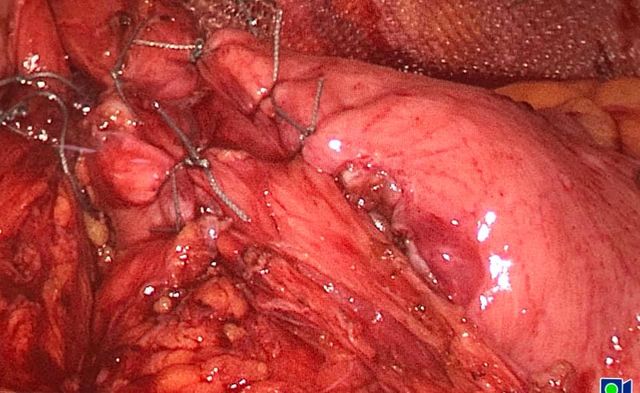

Challenging emergency during the COVID: Child’s A CLD with HUGE gastric varices uncontrolled

Child’s A CLD with HUGE gastric varices uncontrolled by Endoscopic glue and attempted EUS coiling. One salvage option would be TIPSS with balloon vascular occlusion but due to logistics we went for modified sugiura procedure. Splenectomy + Gastro esophageal devascularisation with anterior Gastrotomy and overseeing of gastric varices with pyloroplasty. Images show 1 CECT showing large gastric fundal varices. 2,3,4 Gastro Esophageal devasc 5, 6 Large fundal varices before and after oversewing. 7. Anterior gastrotomy 8. Pyloroplasty. Postoperative recovery was uneventful.